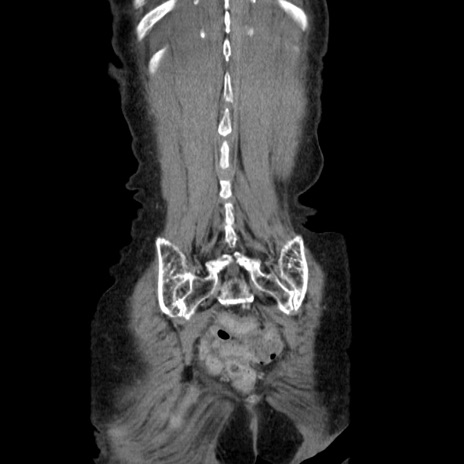

症例25(冠状断像)

【症例】80歳代女性

【主訴】胸のつかえ感

【現病歴】約9時間前に食後から胸のつかえた感じあり、嘔吐あり、来院。

【既往歴】胃癌(全摘)、胆摘、虫垂炎

【身体所見】心窩部に圧痛あり、反跳痛なし。

【データ】WBC 5700、CRP 0.05